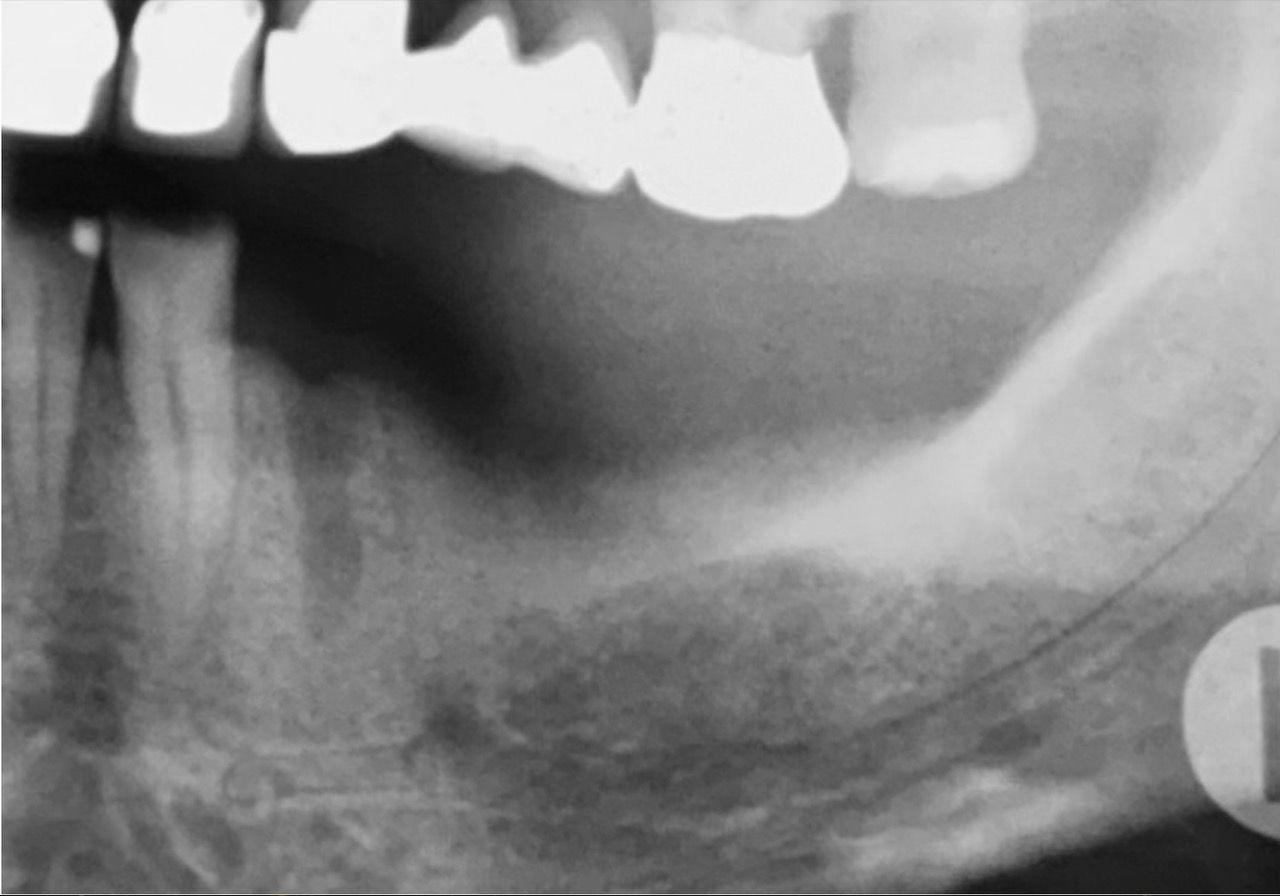

Estrazione di un dente soprannumerario incluso

Visione radiografica

Visione post estrattiva

Dente estratto